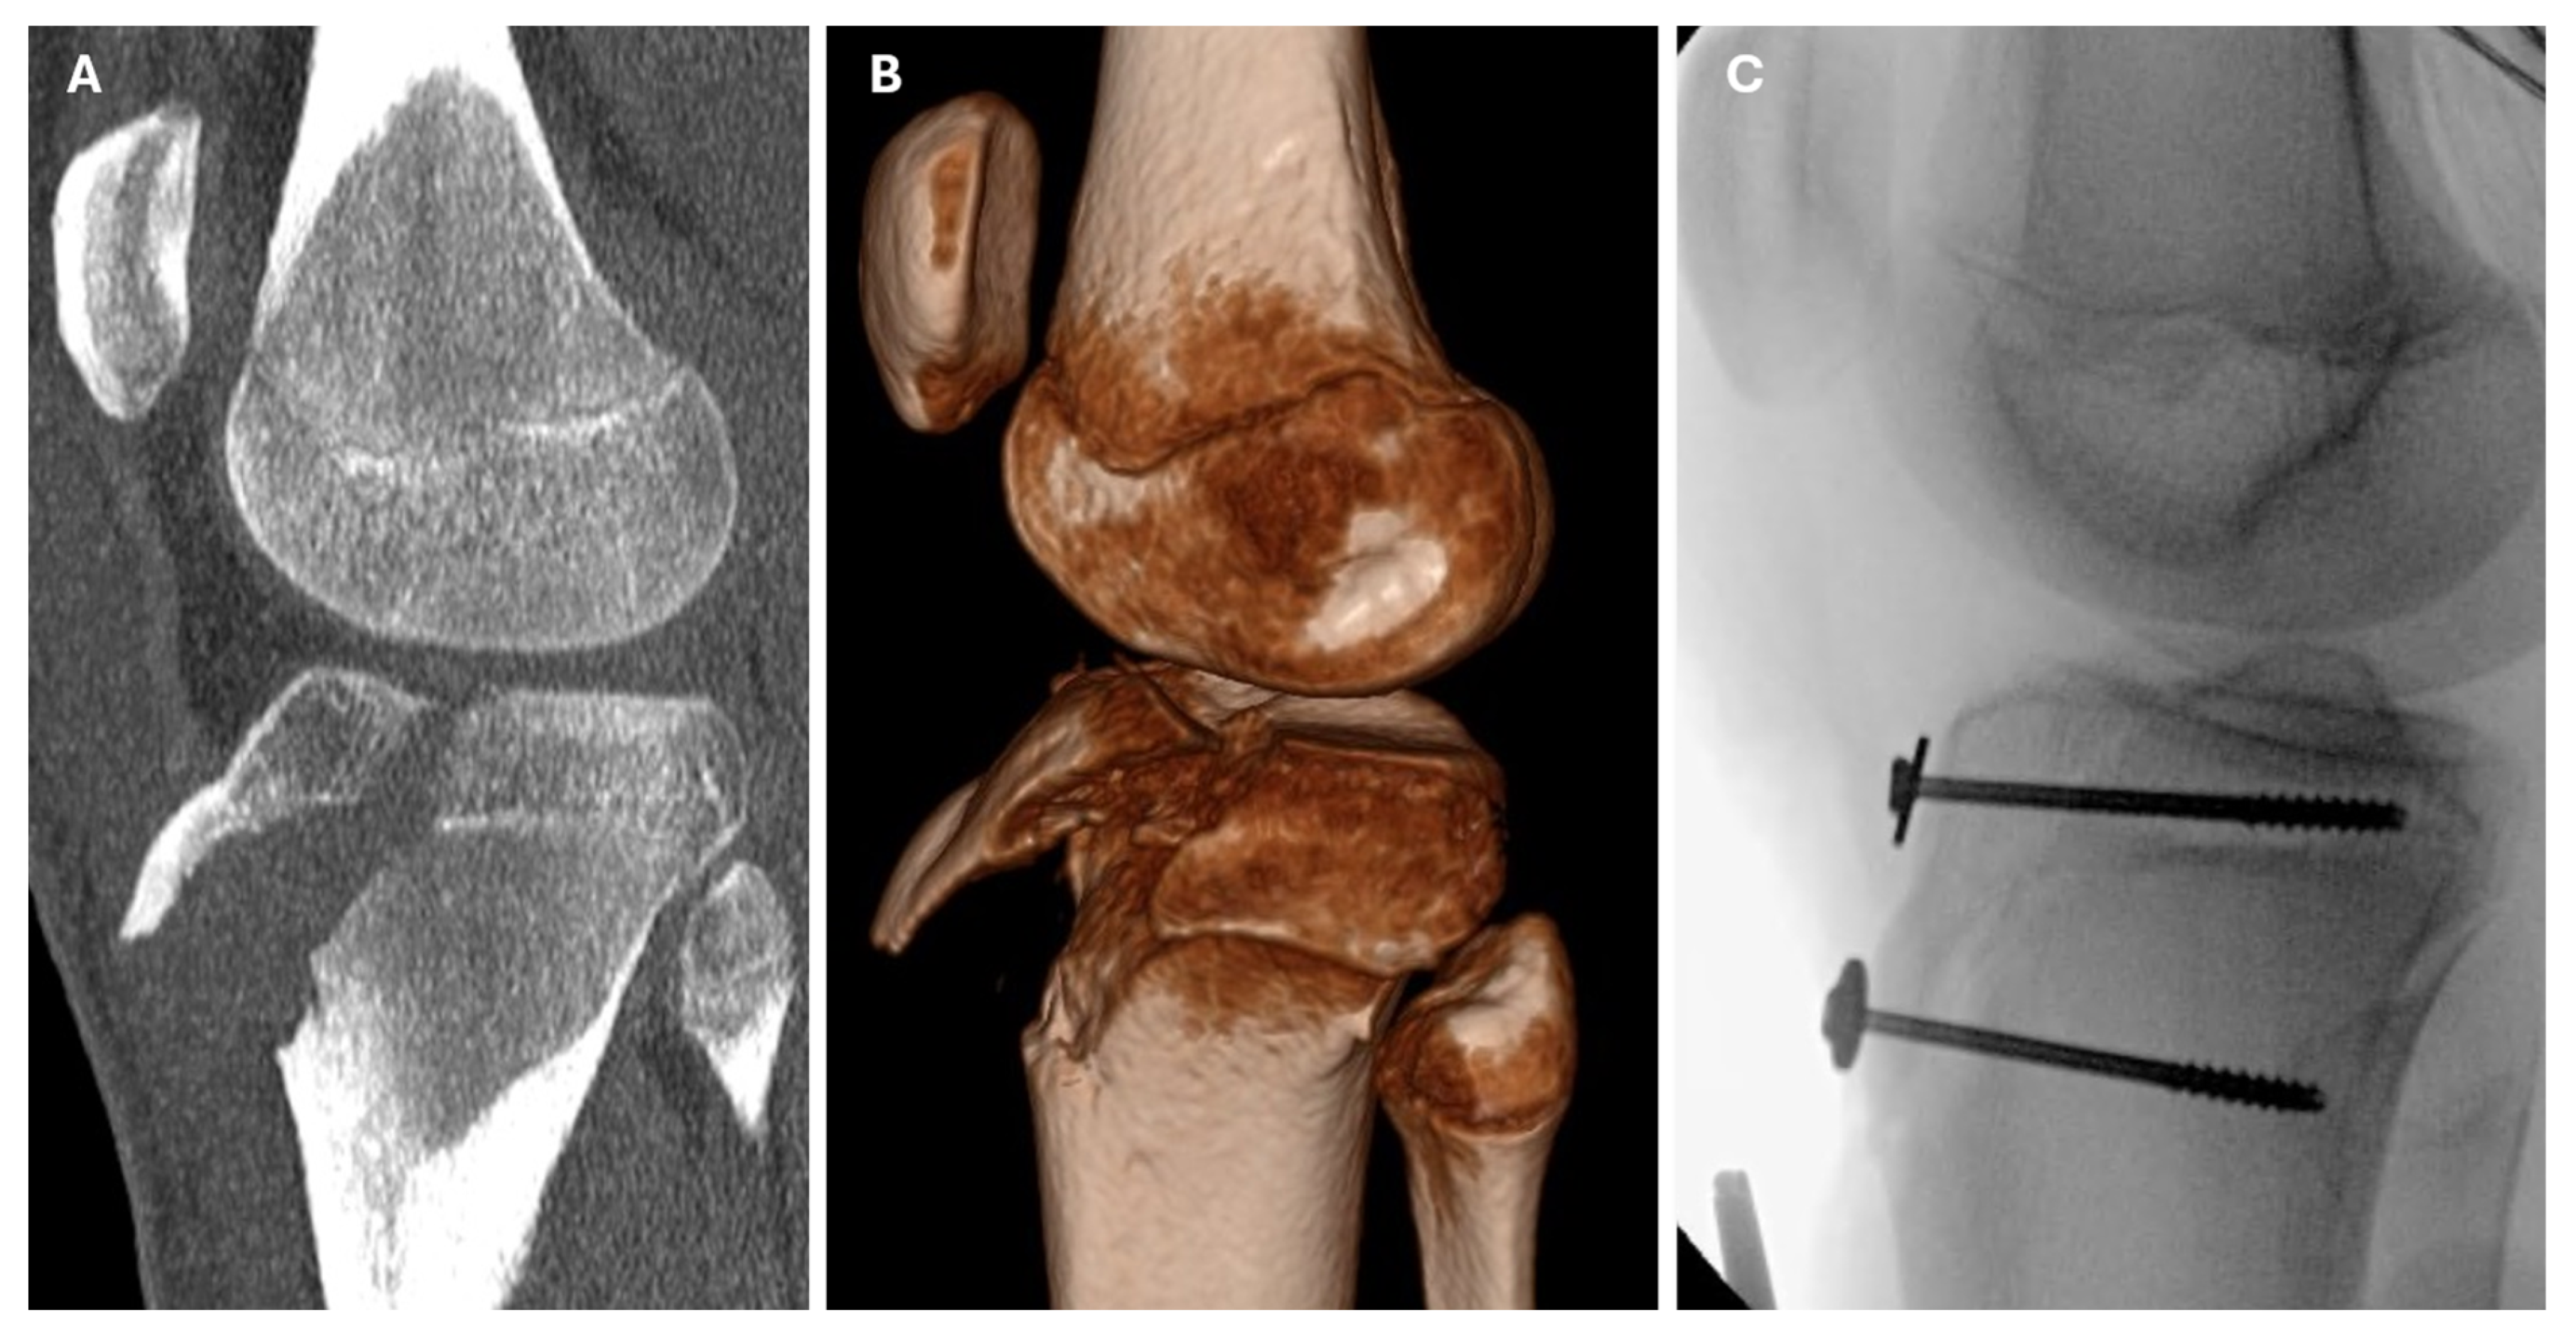

| 5 | Handball | CT | IIIb | ORIF | screws | quadriceps tendon | intra-articular screw prominence | 10.7 |

| 9 | Soccer | CT | IVb | ORIF | screws | patellar ligament | - | 7.8 |